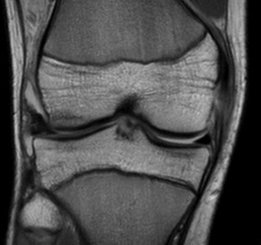

MRI

Classification

Grade I: intact ligament with periligamentous oedema

Grade II: partial tearing with surrounding oedema

Grade III: complete ligament tear

Sites

Femoral avulsion

Midsubstance

Tibial side: wave sign, ensure that the MCL is no flipped above pes anserinus as will not heal (analogous to Stener lesion)

Acute femoral avulsion

Midsubstance MCL tears

Wave sign indicative of tibial avulsion, with ligament retracted above pes anserinus / hamstring tendons

In the chronic setting see thickening of the MCL